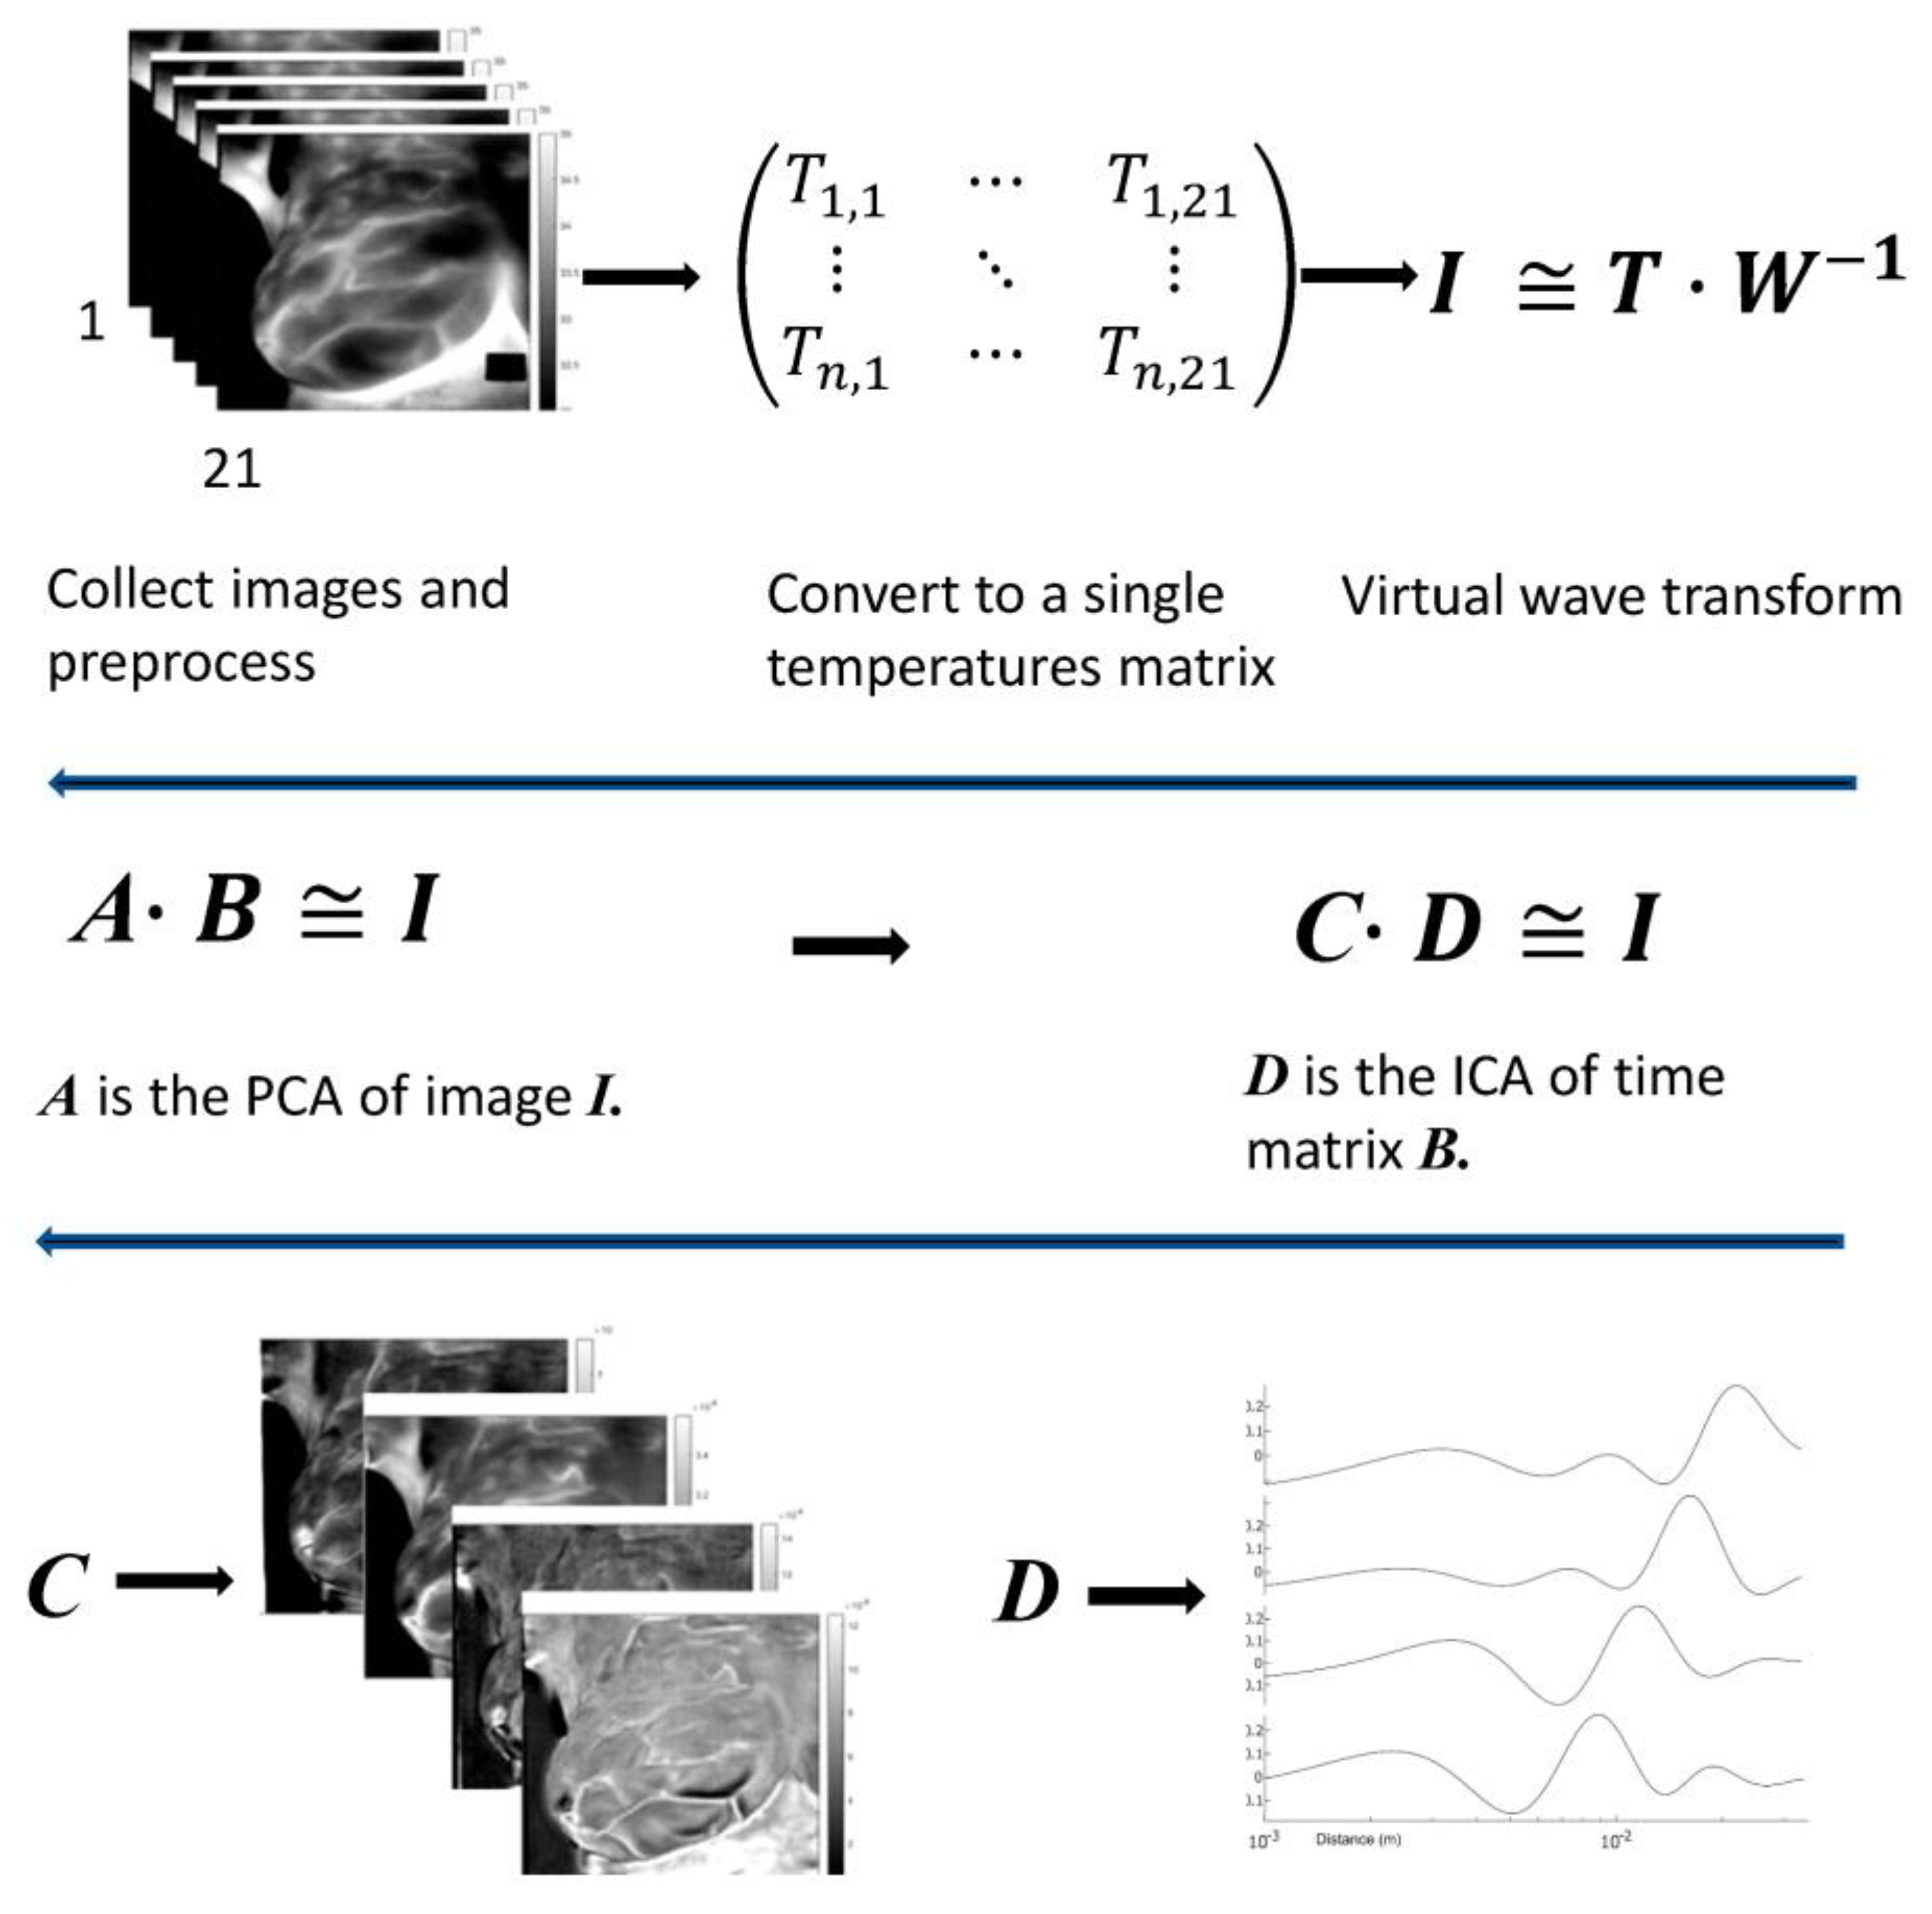

2.2. Approach

2.3. Mathematical Analysis

3.3. Analysis

Appendix A. Virtual Wave Transform (VWT)

Appendix A.1. Virtual Wave

Appendix A.2. Modified Truncated Singular Value Decomposition

Appendix B. Matrix Factorization

Appendix C. Excitation Extraction